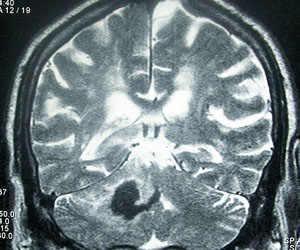

In May 2006, medical regulators in Denmark issued a warning that signaled trouble for General Electric. Danish researchers noted that, over a four-year period, 25 patients in Denmark and Austria had suffered a rare and crippling disease after undergoing an MRI, the scanning procedure used to diagnose everything from brain tumors to blown knees. The patients had been injected with a GE dye that makes images more distinct. They all had weak kidneys before receiving the dye.

The GE product, Omniscan, has since been linked to other cases of the disease, which appears to affect only MRI patients who have kidney problems. Similar drugs made by Bayer and others have also been tied to the sometimes fatal ailment, nephrogenic systemic fibrosis (NSF).

Omniscan and comparable products contain the potentially toxic metal gadolinium. During MRIs, the metal helps physicians see the brain and other parts of the body. Healthy kidneys filter out gadolinium. But patients with severely impaired kidneys can become victims of NSF, according to the FDA.